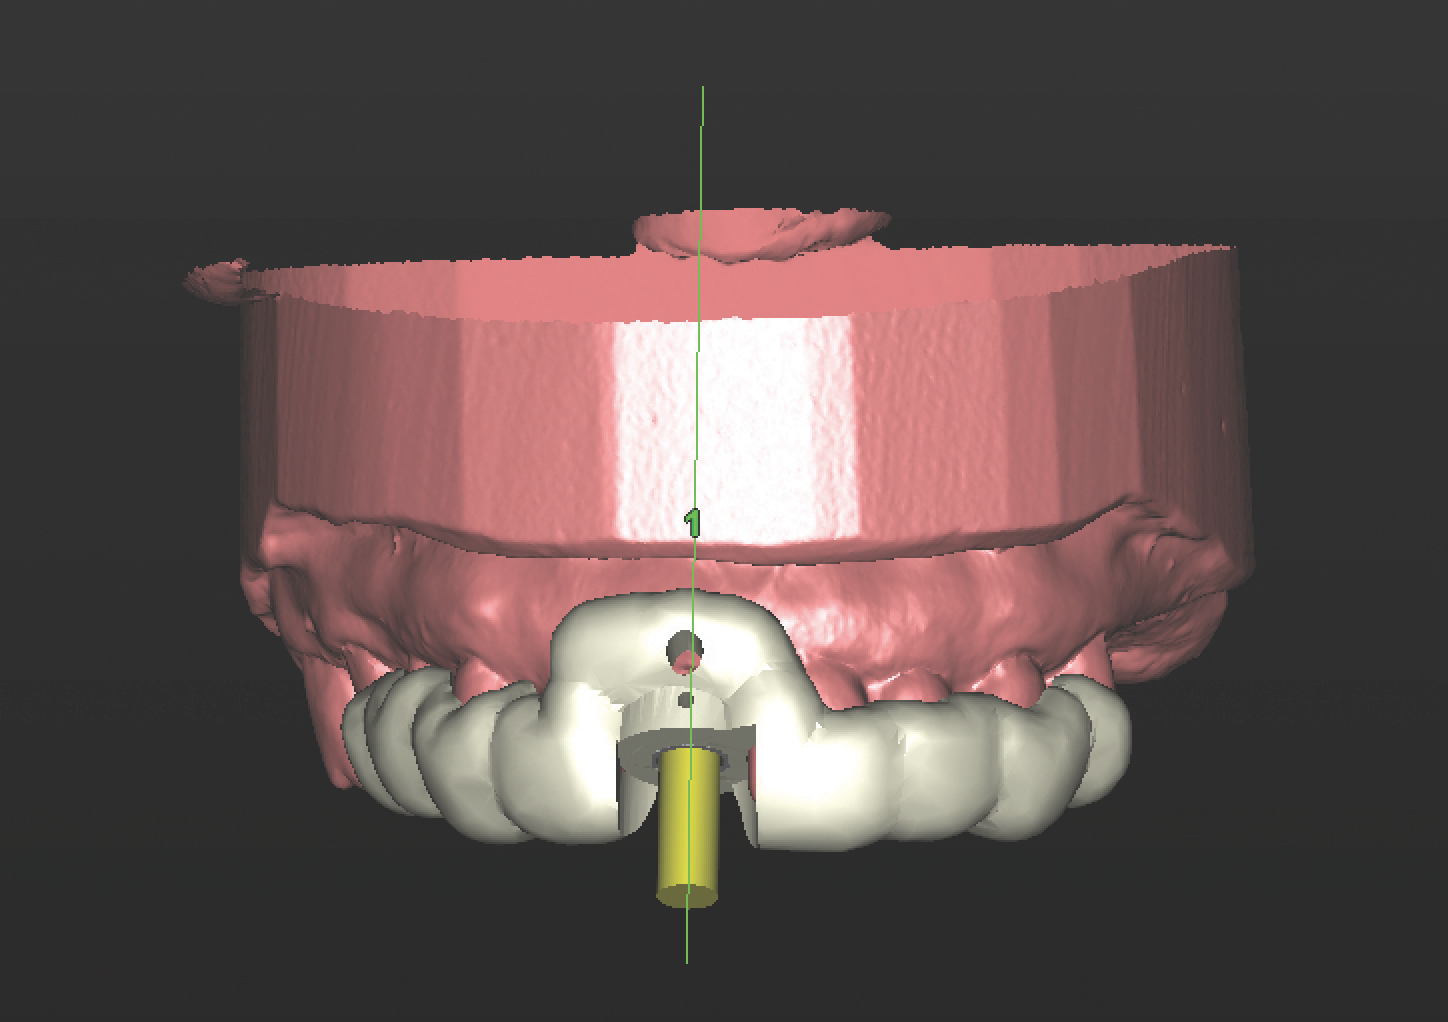

With all of this needed information relative to the pre-operative condition and proposed final tooth position, the treatment moved into the assessment and planning phase. The CBCT revealed an intact buccal plate anterior to the root of tooth No. 8 with adequate bone surrounding the area in all dimensions. Because of the favorable bony contours, an immediately placed implant was decided upon and planned in the software. The CEJ of the proposed final tooth location was identified and an OsseoSpeed EV 4.2 C - 11 mm implant (Dentsply Implants) was planned 3 mm apical and 2 mm lingual to that landmark12 to assure adequate biologic and prosthetic space for the final restoration (Figure 3 through Figure 5). A Simplant SAFE Guide was selected and ordered to convey all of the positional parameters of the final implant position, including depth control and implant timing.

Fig 3 through Fig 5. The Simplant plan of the future implant position 3 mm apical and 2 mm

lingual to the CEJ of the proposed final restoration, including final guide design.

Figure 3

Figure 4

Figure 5